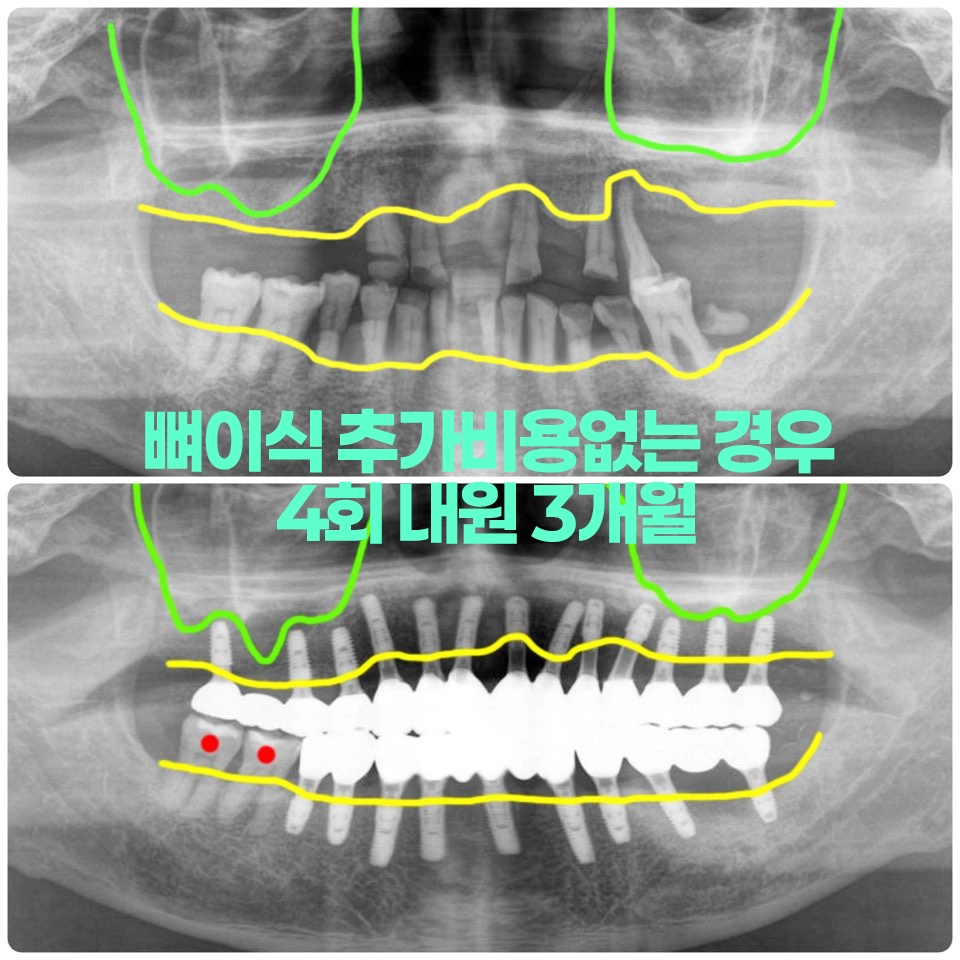

전체임플란트 뼈이식없이 잘하는 방법-염증부위 피해 뼈이식 최소화 치과치료